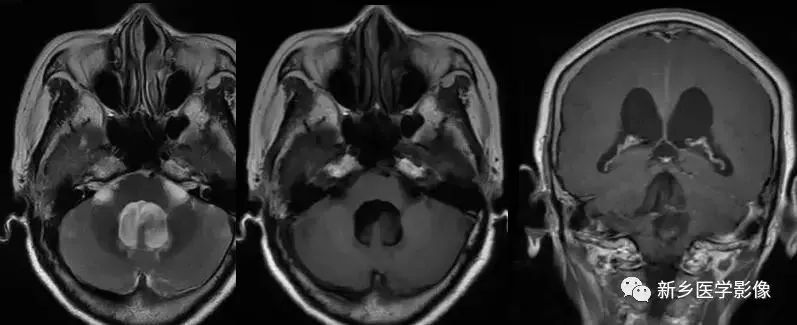

❹ Dandy-Walker’s综合症

又称第四脑室中侧孔先天性闭锁。在胚胎早期期,第四脑室正中孔及侧孔闭寒,导致四脑室呈囊性扩张,并伴有小脑蚓部及半球发育不良,扩张之四脑室向后发展,并与枕大池相连,使后颅窝扩大,小脑幕抬高。本病出现脑积水通常见于婴儿期,或者出生后即存在,但到成人期才发病。